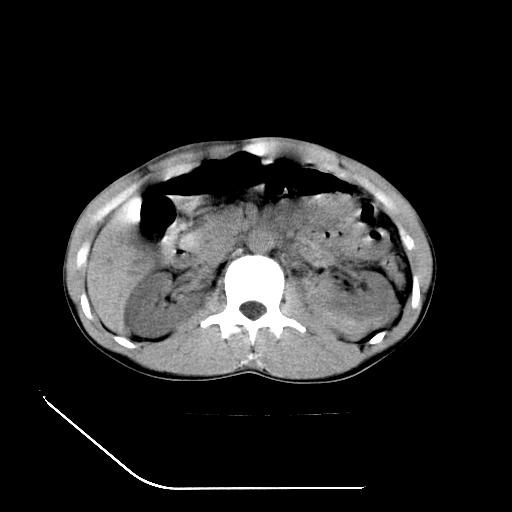

m-25y 高空堕落 12 月5号

12月7号病人尿量200ml/24h 急查双肾ct

左肾挫裂伤并肾周血肿;

肝肾间隙可见液区,建议手术探查;

支持:1、左肾挫裂伤并肾周血肿;

2、少量腹水;

3、左肾旋转不良;

4、反射性肠淤张。

反射性肠郁张是指许多原因造成肠道吸收气体和液 功能障碍,也可造成分泌功能与动力的障碍,以致肠道内有过量的气体和液体潴积,有时只有过量的气体潴积。肠道较舒张,但不扩大,或有部分肠道轻度的扩大,这种情况叫做反射性肠郁张 ,这个病人的肠管扩张太明显了。

提示有肠梗阻的可能性?

综上所述,考虑1:左肾挫伤并包膜下血肿2:少量腹腔积液3:肠梗阻的可能

除了1:左肾挫裂伤并肾周血肿;

2:少量腹水

第二次ct检查后:临床医生腹水穿刺后考虑肠系膜动脉破裂,后实行剖腹探查:于空肠距离十二指肠90cm处发现肠管破裂,破裂口较小;修补后关腹。